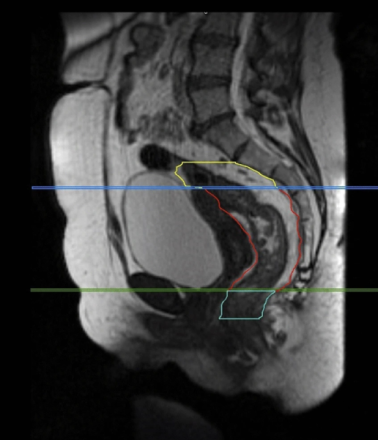

FIGURE 2 from Boldrini et al [7] showing the sagittal view of mesorectal space (in red outline) that is generally included in the target

The IMRT consensus atlas by Lim et al shows the axial view of this mesorectum incorporated into the parametria below. (figure 3). The entire mesorectum is included here (green) because of the tumor involvement of the right uterosacral ligament (shown by arrows) This is best seen on MRI but can also be seen on a good contrast CT simulation [8].

Figure 3